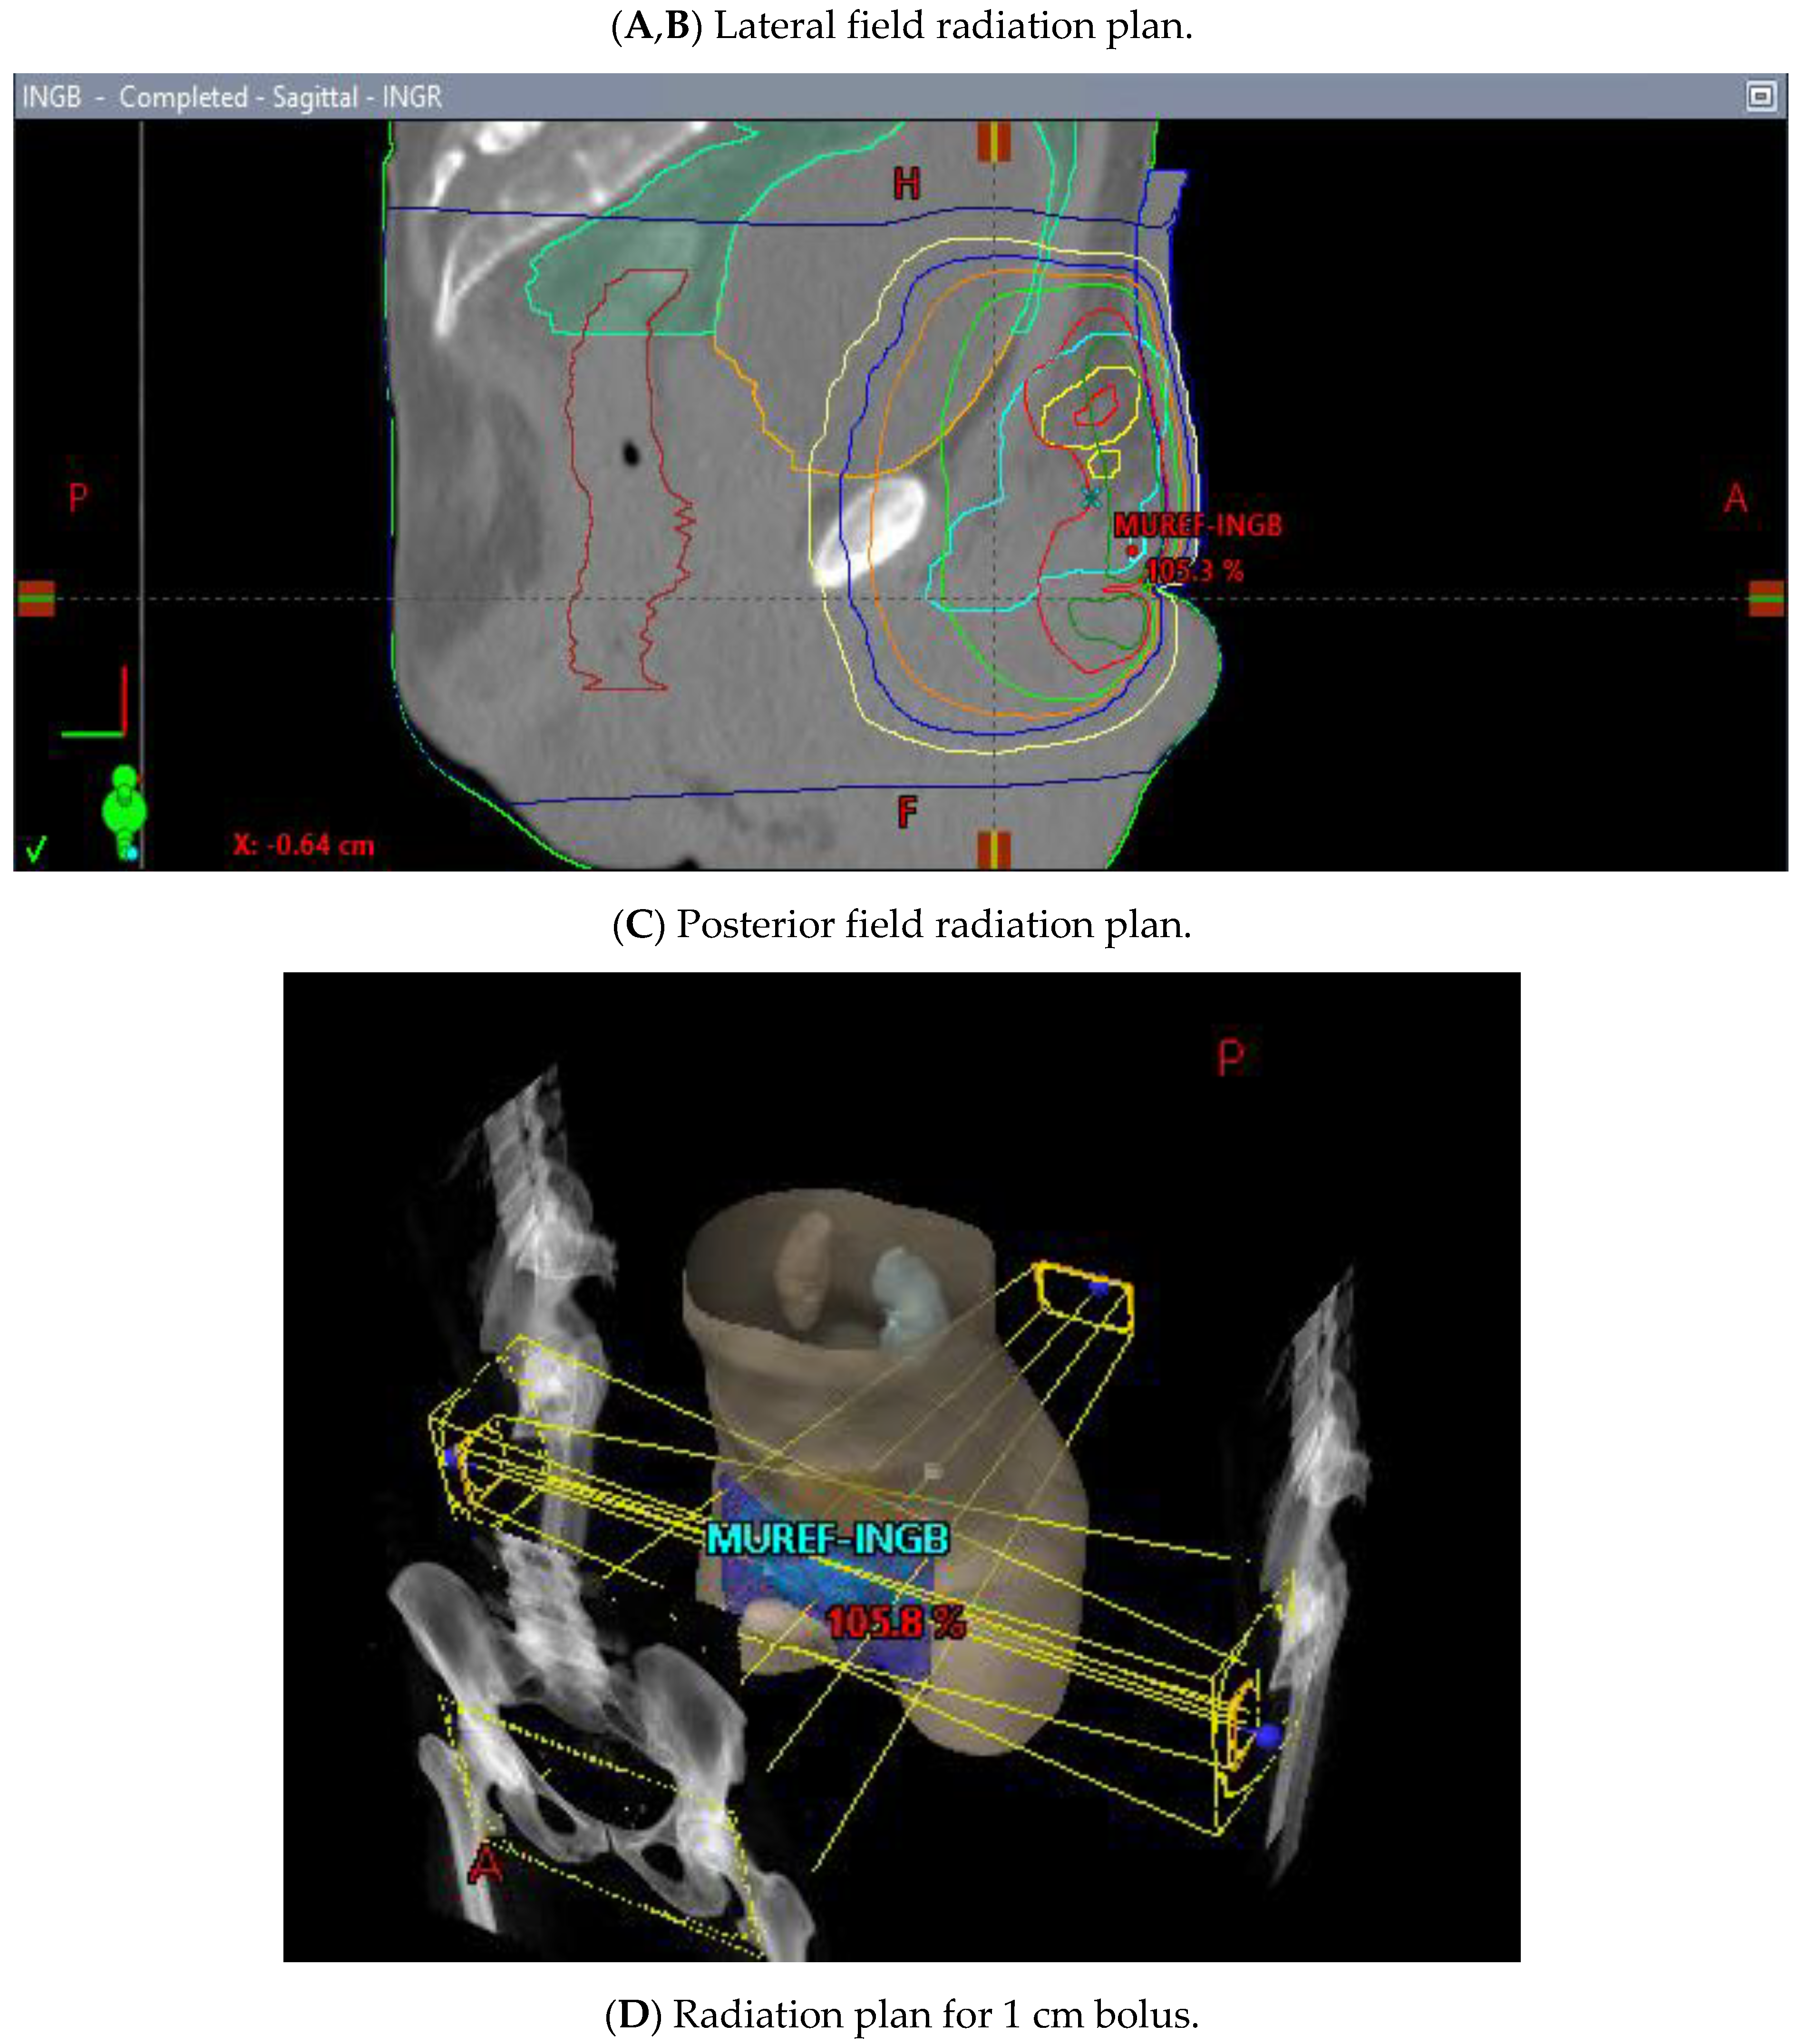

Figure 10.

3 Field (2 laterals (A,B) and 1 posterior (C) field) palliative radiation plan with 20 Gy/5 fractions to the inguinal nodes with a 1 cm bolus (D).

He began dose-reduced FOLFIRI chemotherapy with palliative intent, with the best response being progression after two cycles. His course was also complicated by rapid atrial flutter and hypotension requiring pressors, which were attributed to the progression of the thromboembolic disease, requiring an increase in the anticoagulation dose. Throughout these events, the patient’s principal complaint remained the persistent priapism and associated pain and psychological distress. He was connected to both the palliative care and psychiatry departments and continued follow-up with the urology department, who inserted a suprapubic catheter to reduce the urinary retention. The patient received palliative radiation (20 Gy in 5 fractions) to the groin with the goal of controlling his groin lymphadenopathy, which was thought to be contributing to his priapism (Figure 10A–D). There was a plan to initiate second-line FOLFOX shortly after completing the radiation treatment.